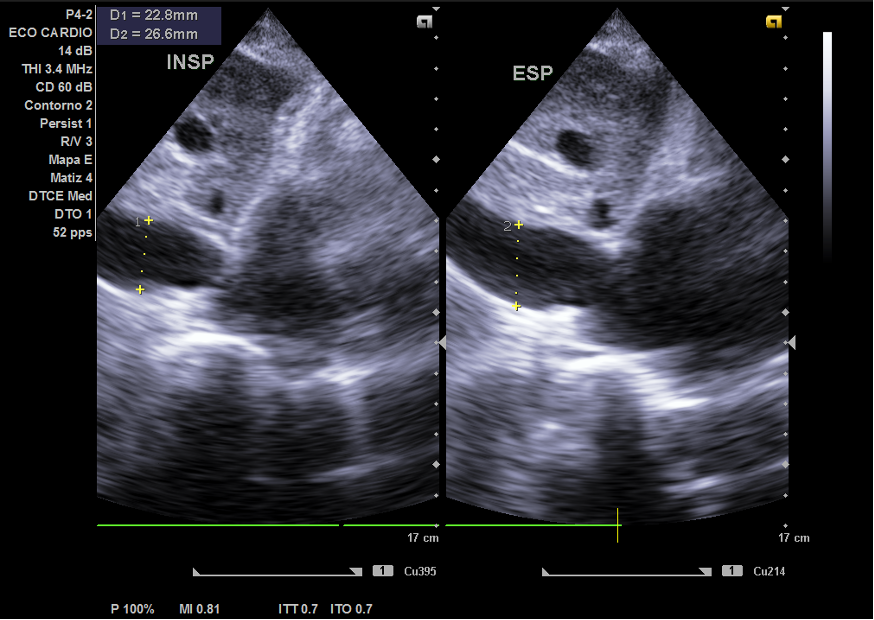

Hallazgos ecográficos

Ecocardiografía: importante dilatación auricular izquierda y derecha, vena cava no colapsable.